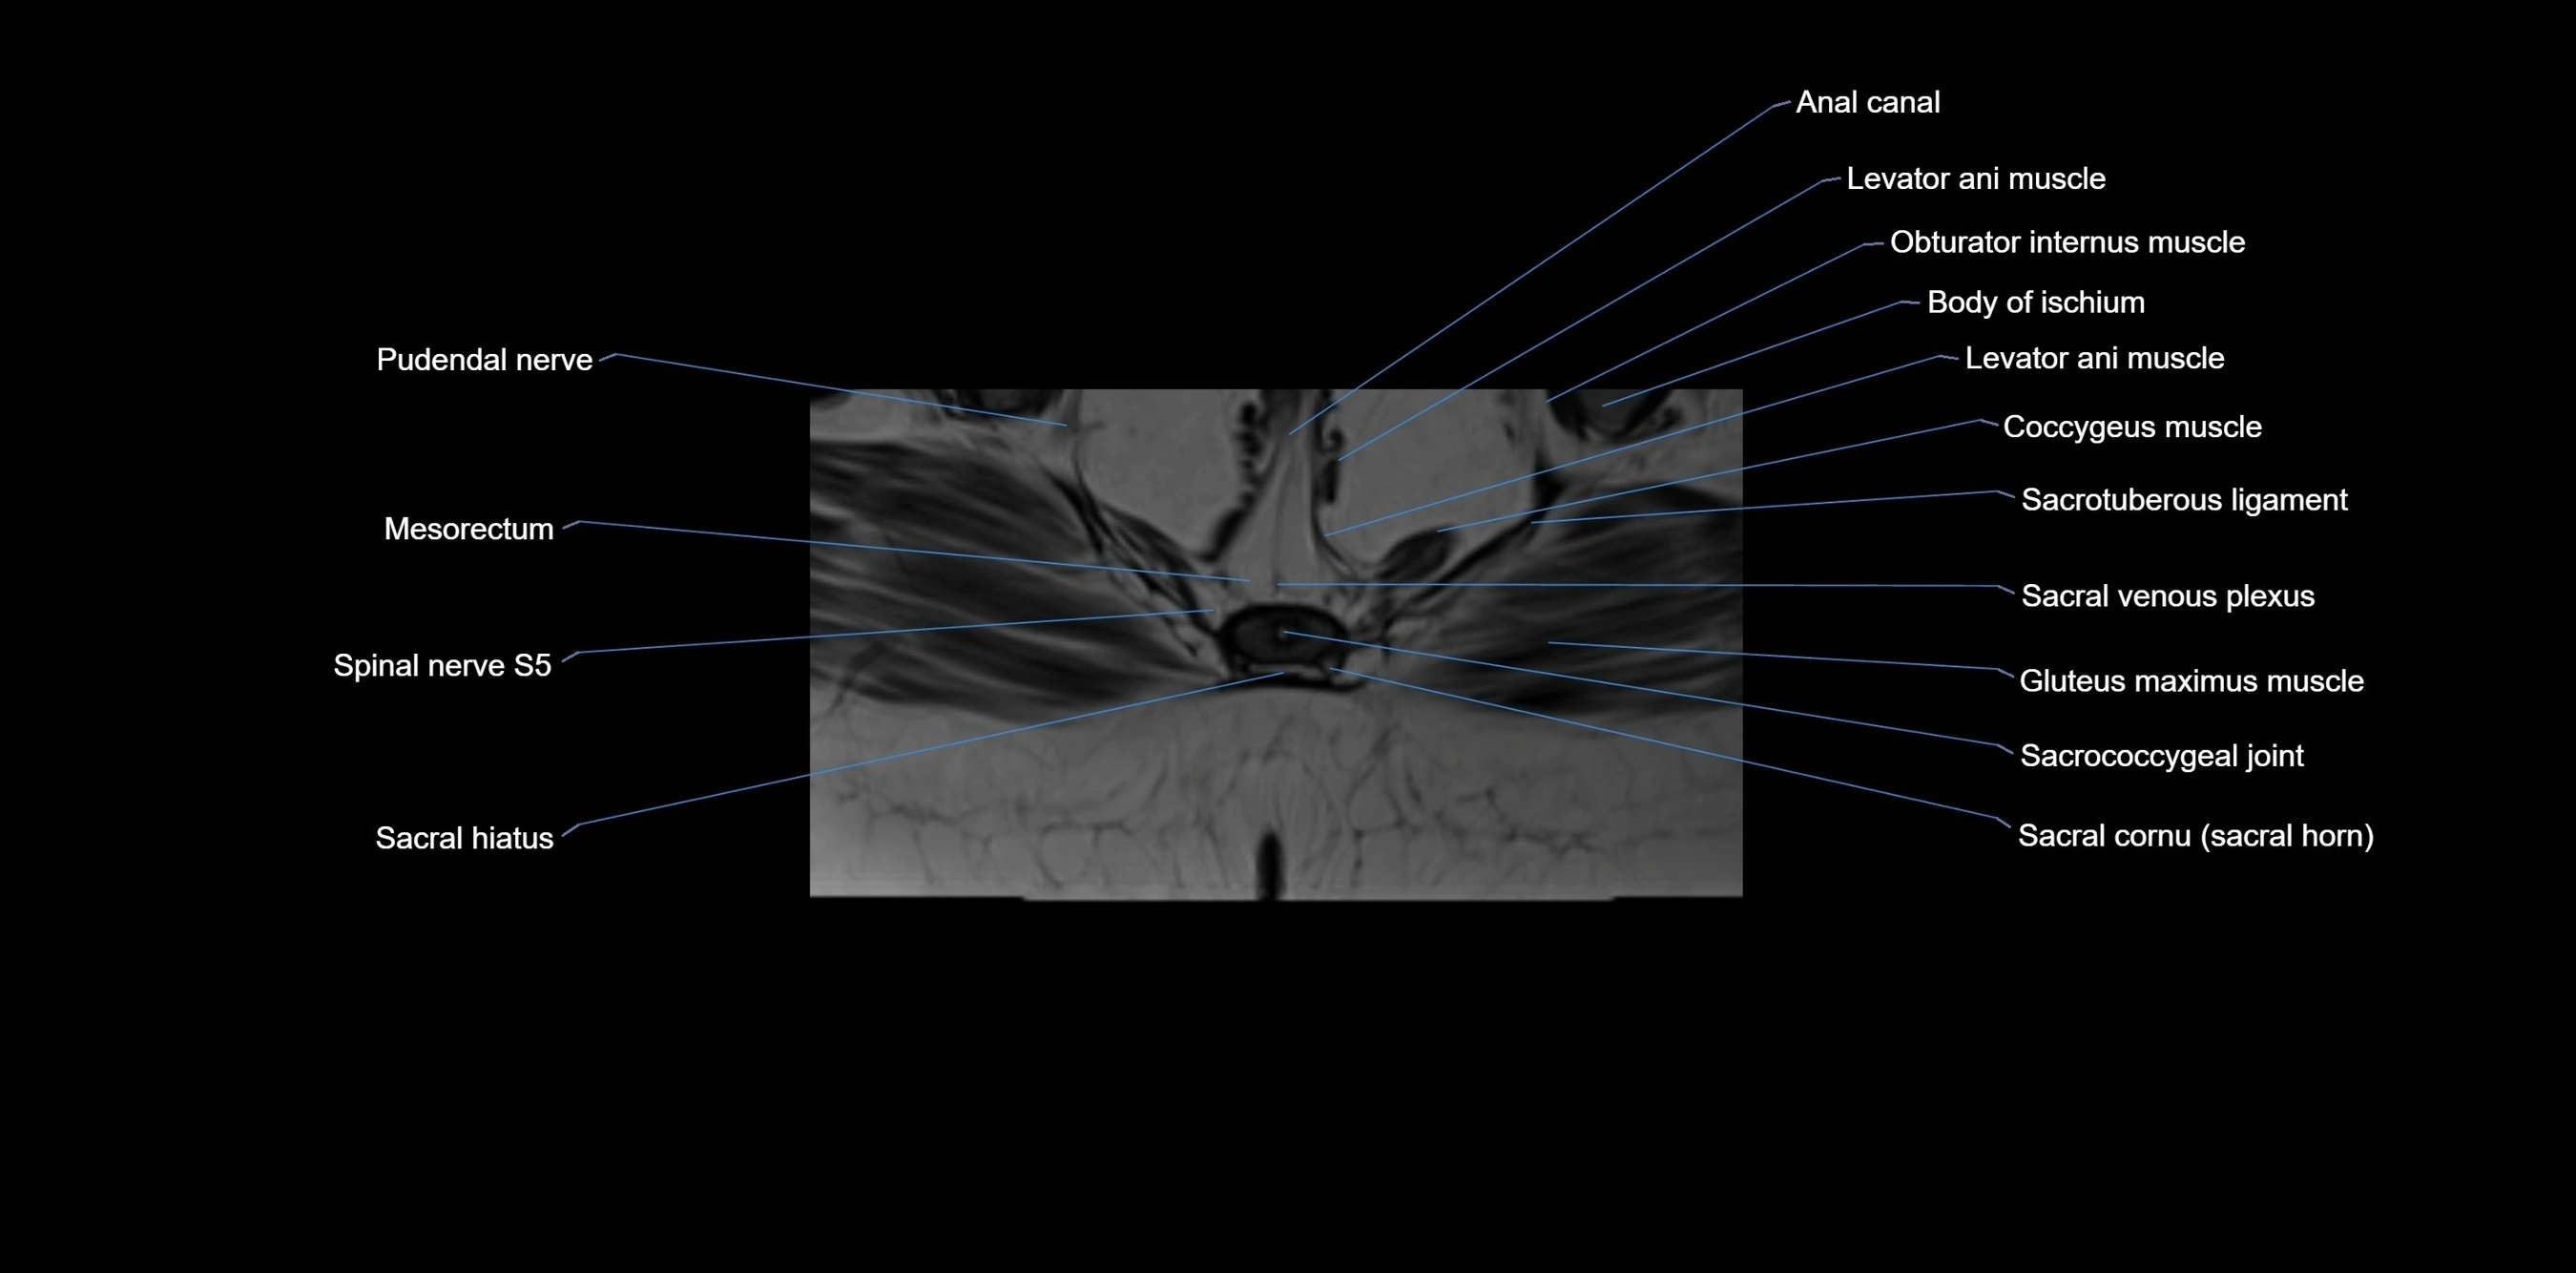

CT VRT image

image